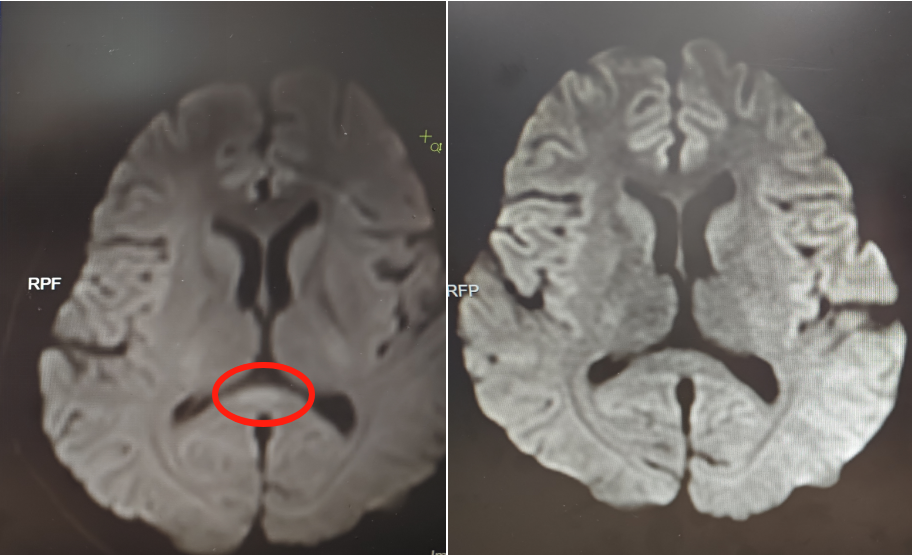

▲治疗前(左)核磁共振提示胼胝体压部病变